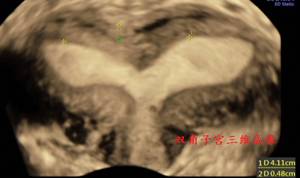

七、双角纵隔子宫

图:双角纵膈子宫三维成像

兼有双角子宫及纵隔子宫的超声特征。ESHRE–ESGE诊断标准:

(1)宫体浆膜层内陷深度>子宫前后壁平均厚度的50%(这条可代替以Troiano及McCarthy提出诊断标准:两侧宫角的内膜顶点连线距宫底浆膜层距离<5mm或越过宫底浆膜层);

(2)浆膜层最低点与宫腔最低点的距离>子宫前后壁平均厚度的150%。